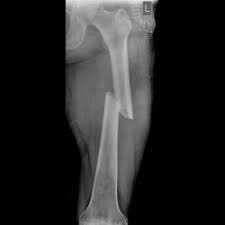

Lecce, frattura di femore nell’anziano, esperti a confronto

femore

Operare una frattura di femore entro 48 ore può fare davvero la differenza. Soprattutto quando il paziente è una persona anziana e, proprio per questo, rappresenta una sfida ancor più cruciale per la capacità di risposta delle organizzazioni sanitarie. Su questo tema di fondamentale importanza, il prossimo sabato 15 giugno 2019 è in programma nel Polo Didattico della ASL Lecce un convegno intitolato "La Frattura di femore nell’anziano: come migliorare l’outcome" (Via Miglietta 5, ore 8,30-16), organizzato dalla SIAARTI - Società Italiana di Anestesia Analgesia Rianimazione e Terapia Intensiva.

In questa ultima sessione si inserisce anche l’interessante parallelo tra l’esperienza della gestione della fratture di femore nel Regno Unito, di cui parlerà il dr. David Marsh, e quella dell’Ospedale "Vito Fazzi" di Lecce, che sarà illustrata dal dr. Giuseppe Rollo (direttore dell’Unità operativa di Ortopedia e Traumatologia). Proprio il nosocomio leccese vanta una percentuale d’interventi chirurgici per frattura di femore eseguiti entro le 48 ore stabilmente attestata oltre il 72 per cento, con una performance quasi raddoppiata rispetto al 2014 (37,89) e sensibilmente superiore alla media italiana (64,74% - fonte Programma Nazionale Esiti 2018).

"Considerata la rilevante incidenza della frattura di femore nei pazienti geriatrici – è la riflessione degli organizzatori - ne consegue un’elevata richiesta di assistenza sanitaria in pazienti fragili. In questi malati la frattura di femore può alterare in maniera significativa l’autonomia del paziente, favorire lo sviluppo di complicanze e compromettere l’aspettativa e qualità di vita. Il conseguente impatto economico e sociale assume dimensioni considerevoli e potenzialmente ancor più rilevanti in un prossimo futuro in ragione del progressivo invecchiamento della popolazione". In questo scenario complesso, l’anestesista "ha un ruolo centrale nella gestione del paziente anziano con frattura di femore, essendo parte attiva non solo nel periodo intra-operatorio, ma anche nella fase di preparazione del paziente e nella gestione del dolore post-operatorio; fasi tutte determinanti per consentire la migliore ripresa funzionale e ridurre le complicanze".